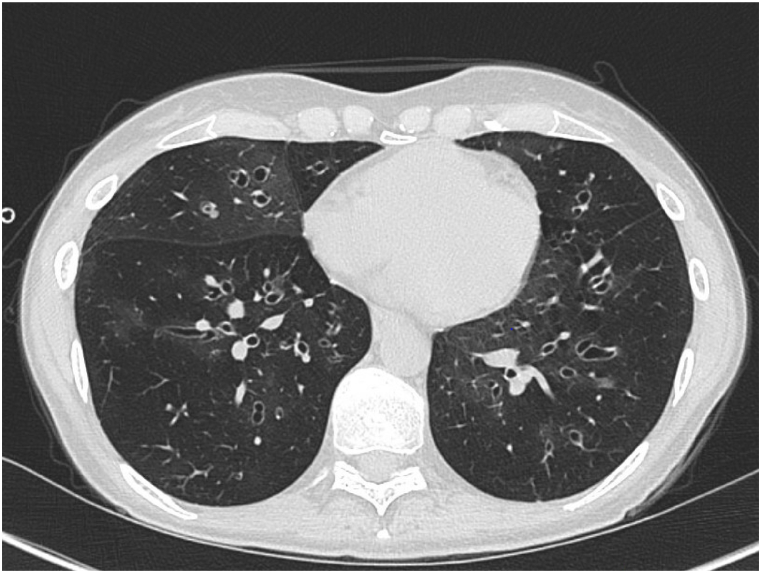

Castlemann disease (CD) is a rare but often benign condition of the lymph nodes. Seldomly coinciding with CD are other conditions, such as paraneoplastic phemhigus (PMP) and bronchiolitis obliterans (BO). When these occur, patients are at risk of developing severe complications, such as respiratory failure, which may subsequently result in death. Diagnosing and managing conditions related to CD poses a challenge and may cause diagnostic delay. In this case report, we describe the course of illness in a 31-year-old female diagnosed with CD. Prior to the diagnosis of CD, the patient had been diagnosed with both paraneoplastic phemfigus and an irreversible airway obstruction. Standard surgical treatment for CD, as well as standard medical treatment for airway obstruction, had little effect. Radiologic findings supported the diagnosis of bronchiolitis obliterans. A progressive decline in pulmonary function eventually led to the patient being evaluated for and undergoing lung transplantation. The co-occurrence of CD and PMP has previously been described as increasing the risk of developing BO, irreversible pulmonary function restrictions and poor prognosis. Lung transplant may be a possible treatment for some patients with terminal respiratory failure.

Abstract Image